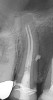

Figure 11. Preoperative radiograph. Courtesy of Dr. Guillaume Jouanny.

Figure 11

Figure 12. Postoperative radiography after full pulpotomy was performed. Courtesy of Dr. Guillaume Jouanny.

Figure 12